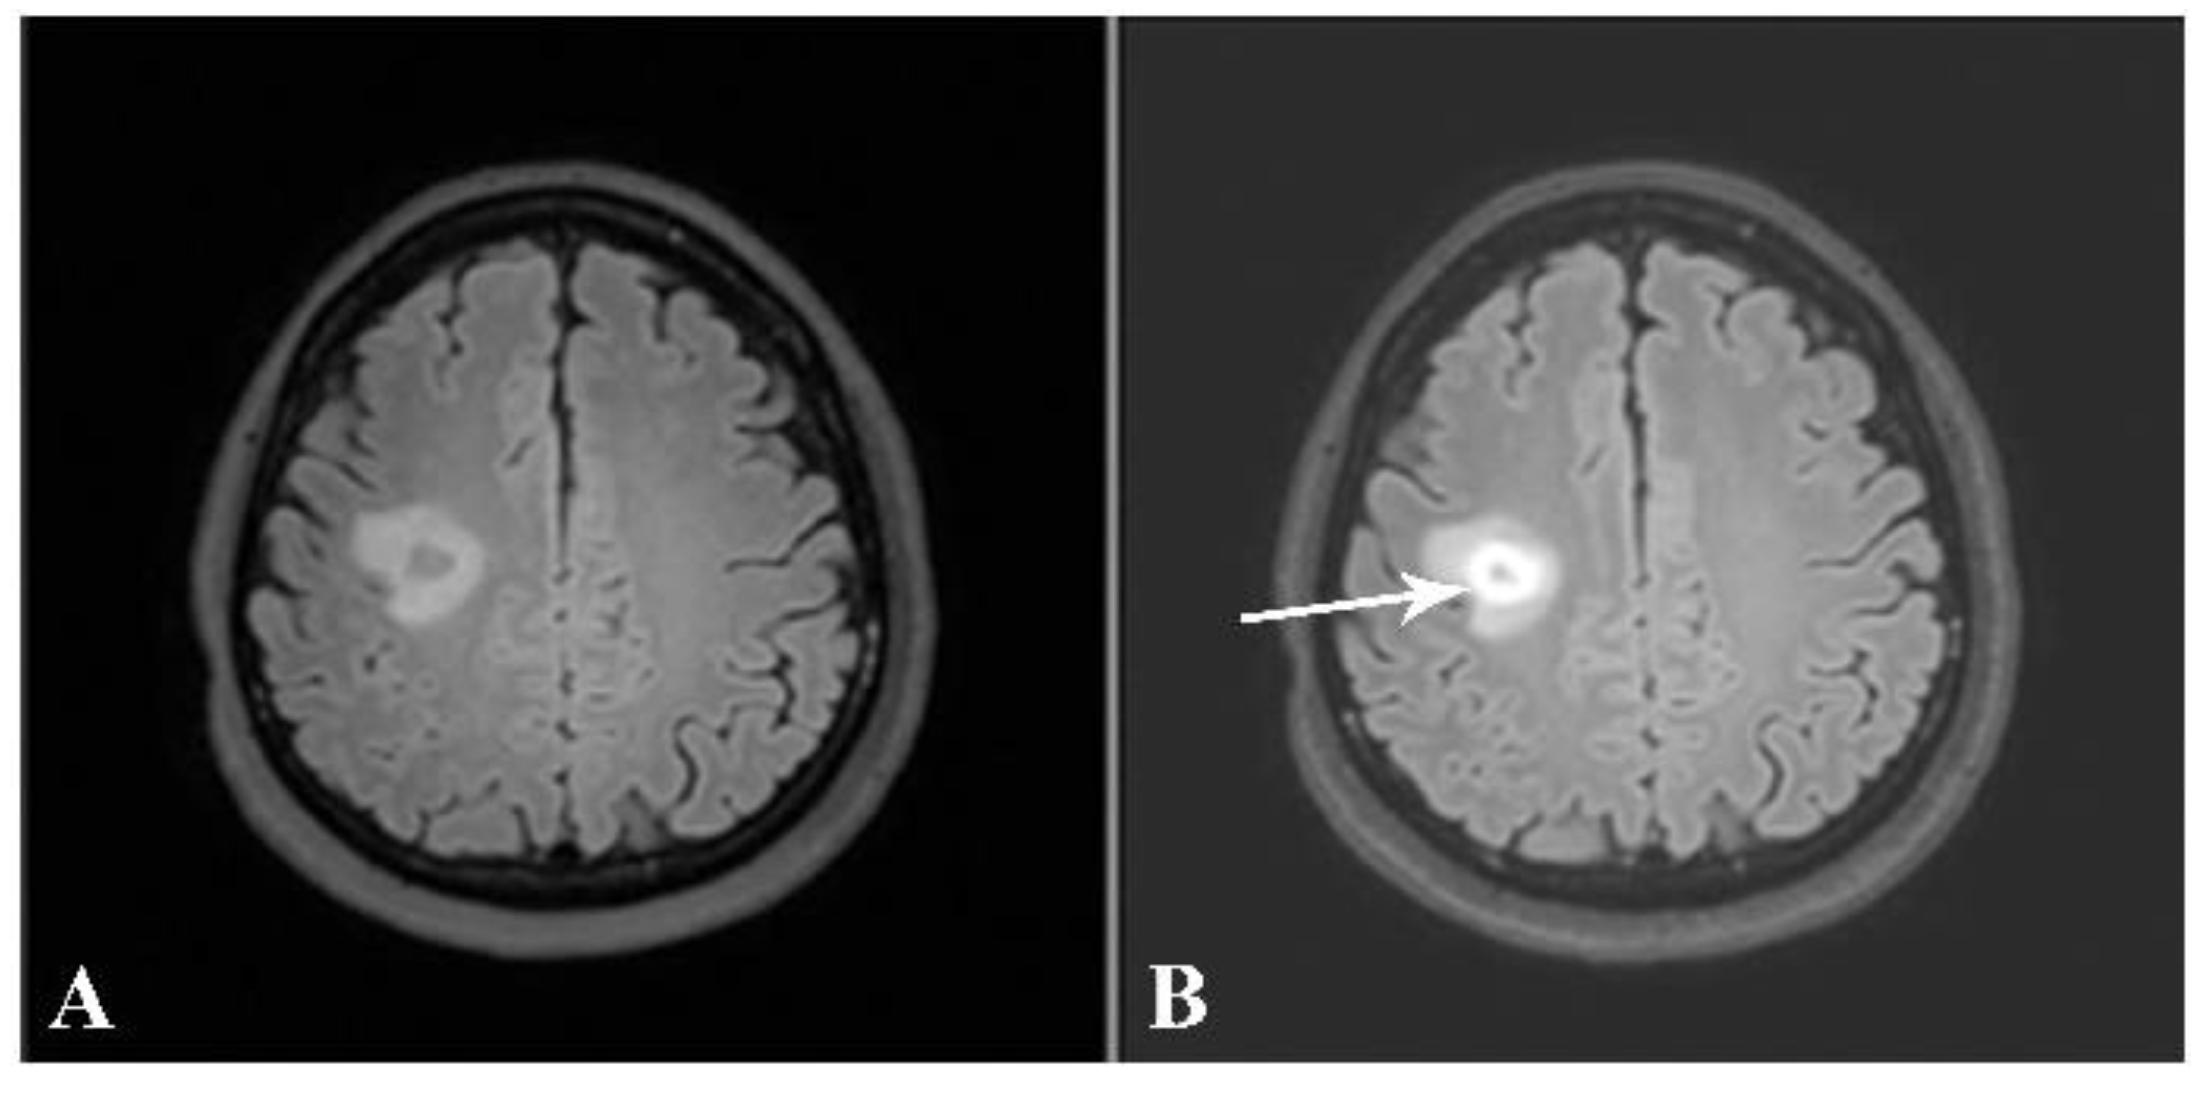

Figure 8. Axial precontrast FLAIR (A) and postcontrast FLAIR (B) images show complete ring-enhancing lesion (arrow) with minimal surrounding vasogenic edema. No significant pressure effect is shown. A presumptive diagnosis of small tumefactive MS was made, although there were no other lesions, either in the brain or in the spinal cord. The patient was given high-dose intravenous steroid.

Taking into consideration each patient’s brain MRI and spinal MRI, if available, dissemination in space (DIS), according to the McDonald criteria, was found in 31 out of the 32 patients (96.9%). The only patient whose MRIs did not demonstrate DIS was the one with a brain MRI typical of tumefactive MS. The patient received a high dose of intravenous methylprednisolone. After follow-up, the lesion decreased in size and no new lesions were detected (Figure 8 and Figure 9).